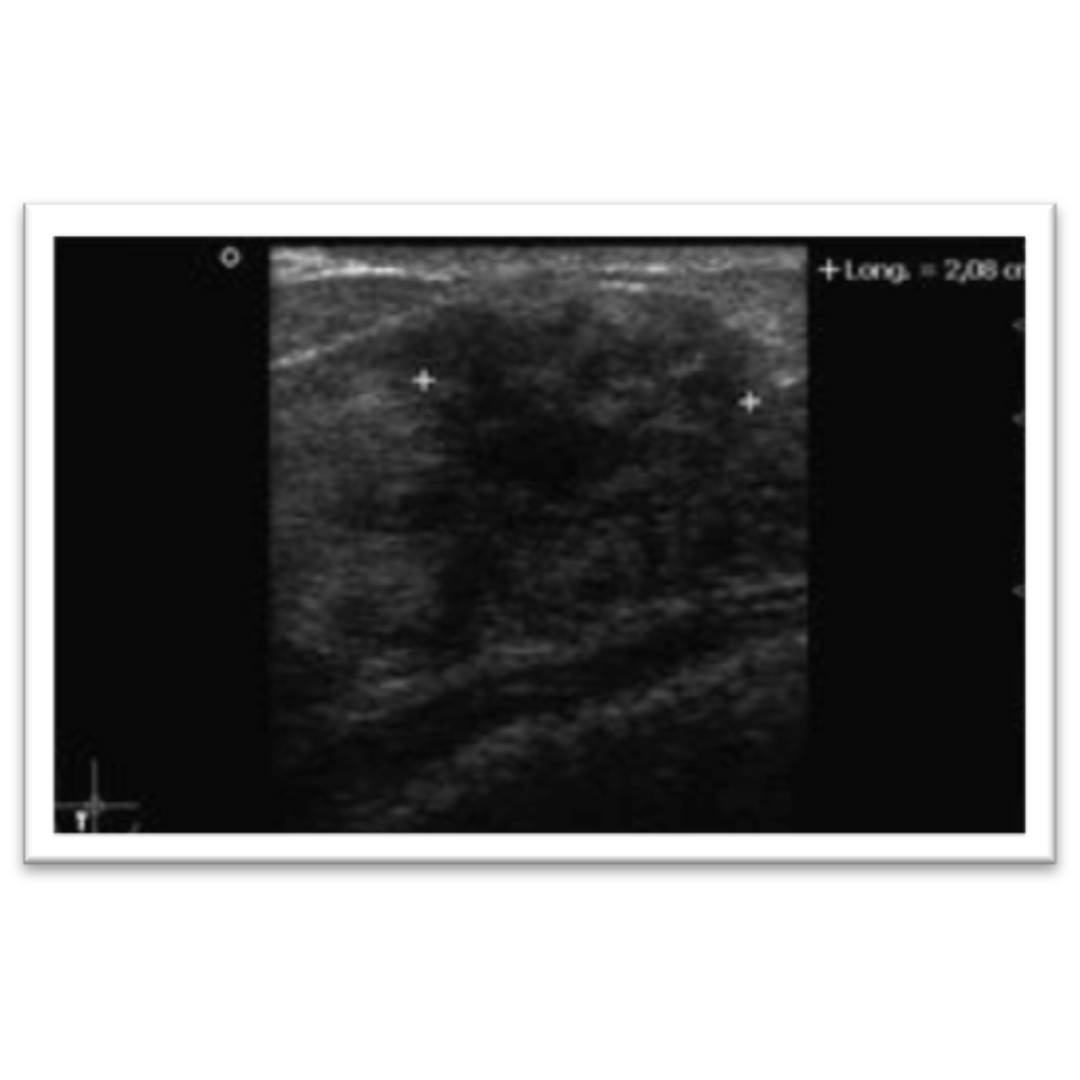

Imagen 3: Imagen nodular de morfología irregular que genera leve sombra acústica posterior, clasificada como BI-RADS 4b.

Es una lesión proliferativa más frecuente en la perimenopausia, se presenta como mastalgia inespecífica e incluso como un bulto palpable. Es hallazgo incidental.

• Al US: imagen nodular de morfología irregular, no paralela, puede generar tenue sombra acústica posterior.

• DD: lesión altamente sospechosa de malignidad al tener características ecográficas de malignidad, comúnmente se necesita una biopsia para confirmar o descartar diagnóstico.